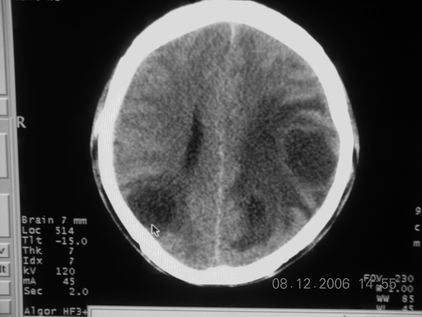

标题: CT11164:男,46岁,白血病患者,,大家看看. [打印本页]

标题: CT11164:男,46岁,白血病患者,,大家看看.

以前的片子,病史忘了,男,46岁,白血病患者,后来到中山二院诊断为

谁见过白血病中枢系统改变是怎么样的吗?

白血病脑浸润。

支持白血病脑浸润.

1 多发脑脓肿可能性大.>2 白血病浸润.

白血病脑浸润。没见过!但结合病史应首先考虑此病。

支持白血病脑浸润

结合病史考虑白血病脑浸润。

结合白血病病史,支持考虑白血病脑浸润。

结合病史考虑白血病脑浸润